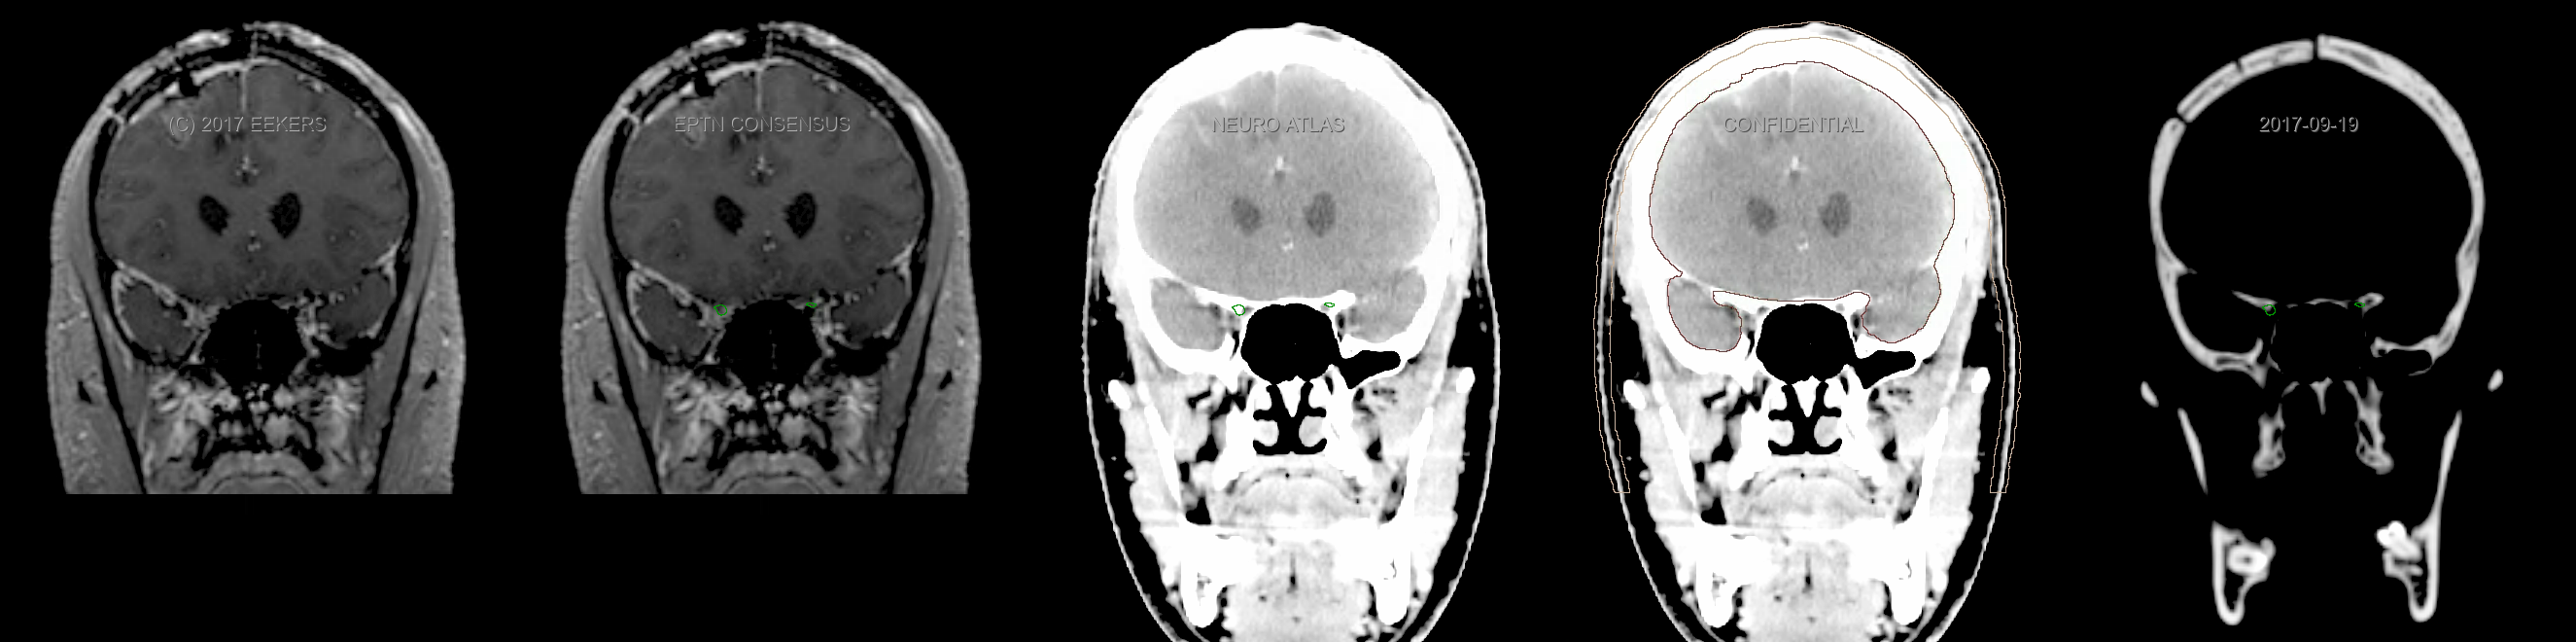

Eekers et al. have published an international neurological atlas for contouring of organs at risk in consensus with the European Particle Therapy Network (EPTN). The purpose of this consensus atlas is to decrease inter- and intra-observer variability in delineating OARs relevant for neuro-oncology. We propose this atlas is used in photon and particle therapy in order to derive consistent dosimetric data. When required this atlas will be updated according to new insights.

Included are all OARs known to be relevant for radiation-induced toxicity in neuro-oncology: brain, brainstem, cochlea, vestibulum & semicircular canals, cornea, lens, retina, lacrimal gland, optic nerve, chiasm, pituitary, hippocampus and skin. A new OAR relevant for neuro-cognition, the posterior cerebellum is also included.

Three-dimensional delineation of the fifteen consensus OARs for neuro-oncology are shown on CT and 3 Tesla (3T) MR images (slice thickness 1 mm with intravenous contrast agent). All are presented in transversal, sagittal and coronal view.

From left to right: MR without structures, MR with structures, CT (WW/WL 120/40) with structures, CT (WW/WL 120/40) with Brain and Brainstem Surface, CT (WW/WL 1500/120)with structures